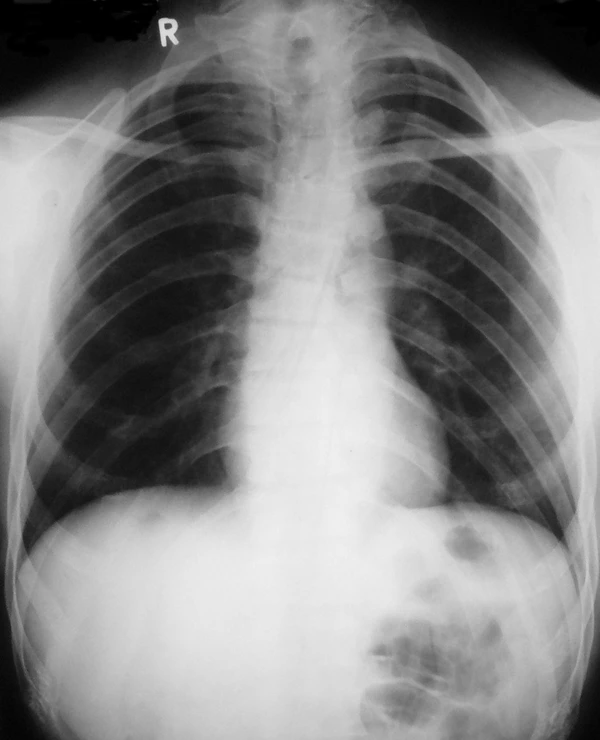

- Недоразвитие или отсутствие одной или обеих ключиц. При отсутствии или недоразвитии ключицы плечевой пояс резко сужен, надплечья покаты и опущены. Отмечается избыточная подвижность в плечевых суставах, возможно даже соприкоснуться плечами спереди грудины.

Диагностика ключично-черепного дизостоза основана на клинических симптомах и рентгенологических исследованиях, которые включают изображения черепа, грудной клетки, таза и рук.

Главный рентгенологический симптом — дефекты ключиц. Обычно отсутствует наружный (акромиальный) конец ключицы, в то время как внутренний (грудинный) конец присутствует. Но иногда ключица состоит из двух фрагментов. Полное отсутствие ключицы встречается редко[4].